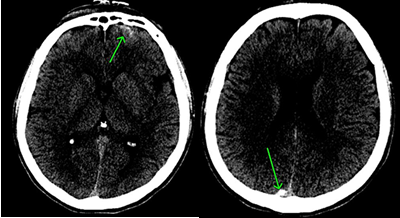

⑧ 急性硬膜下血腫

【CT画像】

【MRI画像】

画像は巨大な三日月型の急性硬膜下血腫です。

急性硬膜下血腫は、頭蓋骨のすぐ内側で脳を覆っている硬膜と脳の間に出血がたまって血腫となったものです。交通事故外傷でよくある傷病名です。

脳挫傷や脳表の小さな血管による出血が脳の表面と硬膜の間に流れ込み、短時間のうちにゼリー状に固まり脳を圧迫します。これが急性硬膜下血腫となります。

血腫による圧迫と脳挫傷のために頭蓋内圧力が亢進すると、激しい頭痛、嘔吐、意識障害などが生じます。血腫による圧迫によって脳ヘルニア状態にまで進行し、深部にある脳幹が侵されて呼吸障害などを生じるようになると、最悪の場合には死に至ります。

受傷当初は意識障害がない例でも、一旦意識障害が発現するとその後は急激に悪化することが多く、予後はきわめて不良です。

血種の外科手術後も脳挫傷が伴うときは、後遺障害となることが多いです。